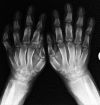

Summary: A 20-year-old man with an 8-year history of progressive enlargement of his hands and feet, coarsening facial features, painful joints and thickened, oily skin was referred for investigation of acromegaly. On examination, the subject was of normal height and weight. He had markedly increased skin thickness around the forehead, eyelids and scalp with redundant skin folds. Bilateral painful knee swelling was accompanied by enlargement of the extremities, and his fingers were markedly clubbed. Routine hematological, biochemical and hormonal blood tests, including GH and IGF-1 were normal. The clinical picture suggested primary hypertrophic osteoarthropathy (PHOA) rather than acromegaly and radiological studies were supportive of this, demonstrating increased subperiosteal bone formation and increased bone density and cortical thickening. There was widespread joint disease, with narrowing of joint spaces, whereas the knees demonstrated effusions and calcification. A skull X-ray revealed calvarial hyperostosis and a normal sellar outline. Family history was negative. Genetic studies were performed on peripheral blood leukocyte DNA for mutations in the two genes associated with PHOA, 15-hydroxyprostaglandin dehydrogenase (HPGD; OMIM: 601688) and solute carrier organic anion transporter family member 2A1 (SLCO2A1; OMIM: 601460). The sequence of HPGD was normal, whereas the subject was homozygous for a novel pathological variant in SLCO2A1, c.830delT, that predicted a frameshift and early protein truncation (p.Phe277Serfs*8). PHOA, also known as pachydermoperiostosis, is a rare entity caused by abnormal prostaglandin E2 metabolism, and both HPGD and SLCO2A1 are necessary for normal prostaglandin E2 handling. High prostaglandin levels lead to bone formation and resorption and connective tissue inflammation causing arthropathy, in addition to soft tissue swelling.